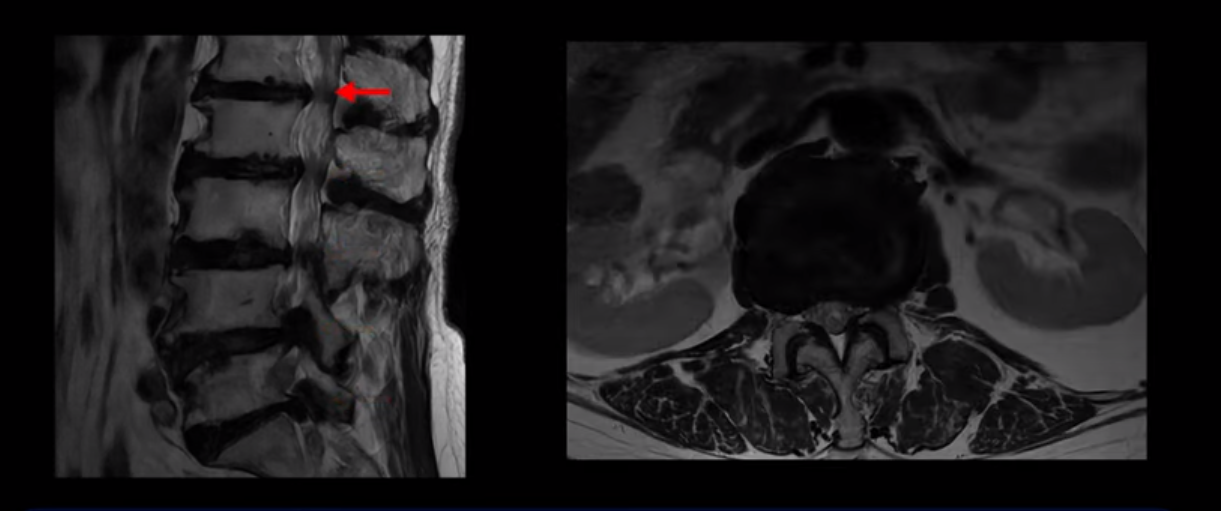

이 환자분은 MRI로 보면 허리 여러 마디가 신경이 매우 심하게 눌려 보이는 분입니다. 이분 MRI를 보면서 간단히 설명해 드린 후 어떻게 이렇게 신경이 심하게 눌린 환자분이 수술 없이 근육신경재활치료로 좋아질 수 있는지, 다리가 아파 걷지 못하는 환자가 어떻게 안 아프고 잘 걸을 수 있게 되는지, 10년 동안 괴로웠던 양 발의 시린 증상은 어떻게 사라질 수 있는지, 치료는 어떻게 하는지 자세히 설명 드리겠습니다.

MRI 보시면 (2-8) 허리의 5마디가 전부 다 심하게 퇴행되어 있습니다.

5마디 전부 다 심한 중심성 협착이 있습니다.

이렇게 모두 다 심하게 막히는 경우는 드문데요. 또한 오른쪽, 왼쪽 신경이 빠져나가는 추간공도 다 심하게 막혀있습니다.

오른쪽, 왼쪽 이렇게 신경 구멍들이 다 좁아지고 신경이 눌리니까 양쪽 다리가 발바닥까지 아파서 걷기 어렵고 양쪽 발이 10년 넘게 시린 겁니다. 당연히 수술해서 눌린 신경을 풀어줘야 한다고 들으셨는데요. 이런 환자분을 어떻게 수술 없이 치료할까요? 지금부터 설명해 드립니다.

이분 신경이 눌리는 증상은 오래됐지만, 증상이 아주 심해진 건 올해 들어와서입니다. 그럼, 이분 MRI 영상도 이렇게 심하게 안 좋아진 게 올해 들어와서일까요? 이분의 MRI로 보이는 협착은 아주 오래된 겁니다. 그래서 신경 구멍이 심하게 좁아진 것도 올해가 아니고 오래된 겁니다. 작년, 재작년에 훨씬 덜 아팠을 때 MRI를 찍었어도 신경 구멍 좁은 정도는 별반 차이가 없었을 겁니다.